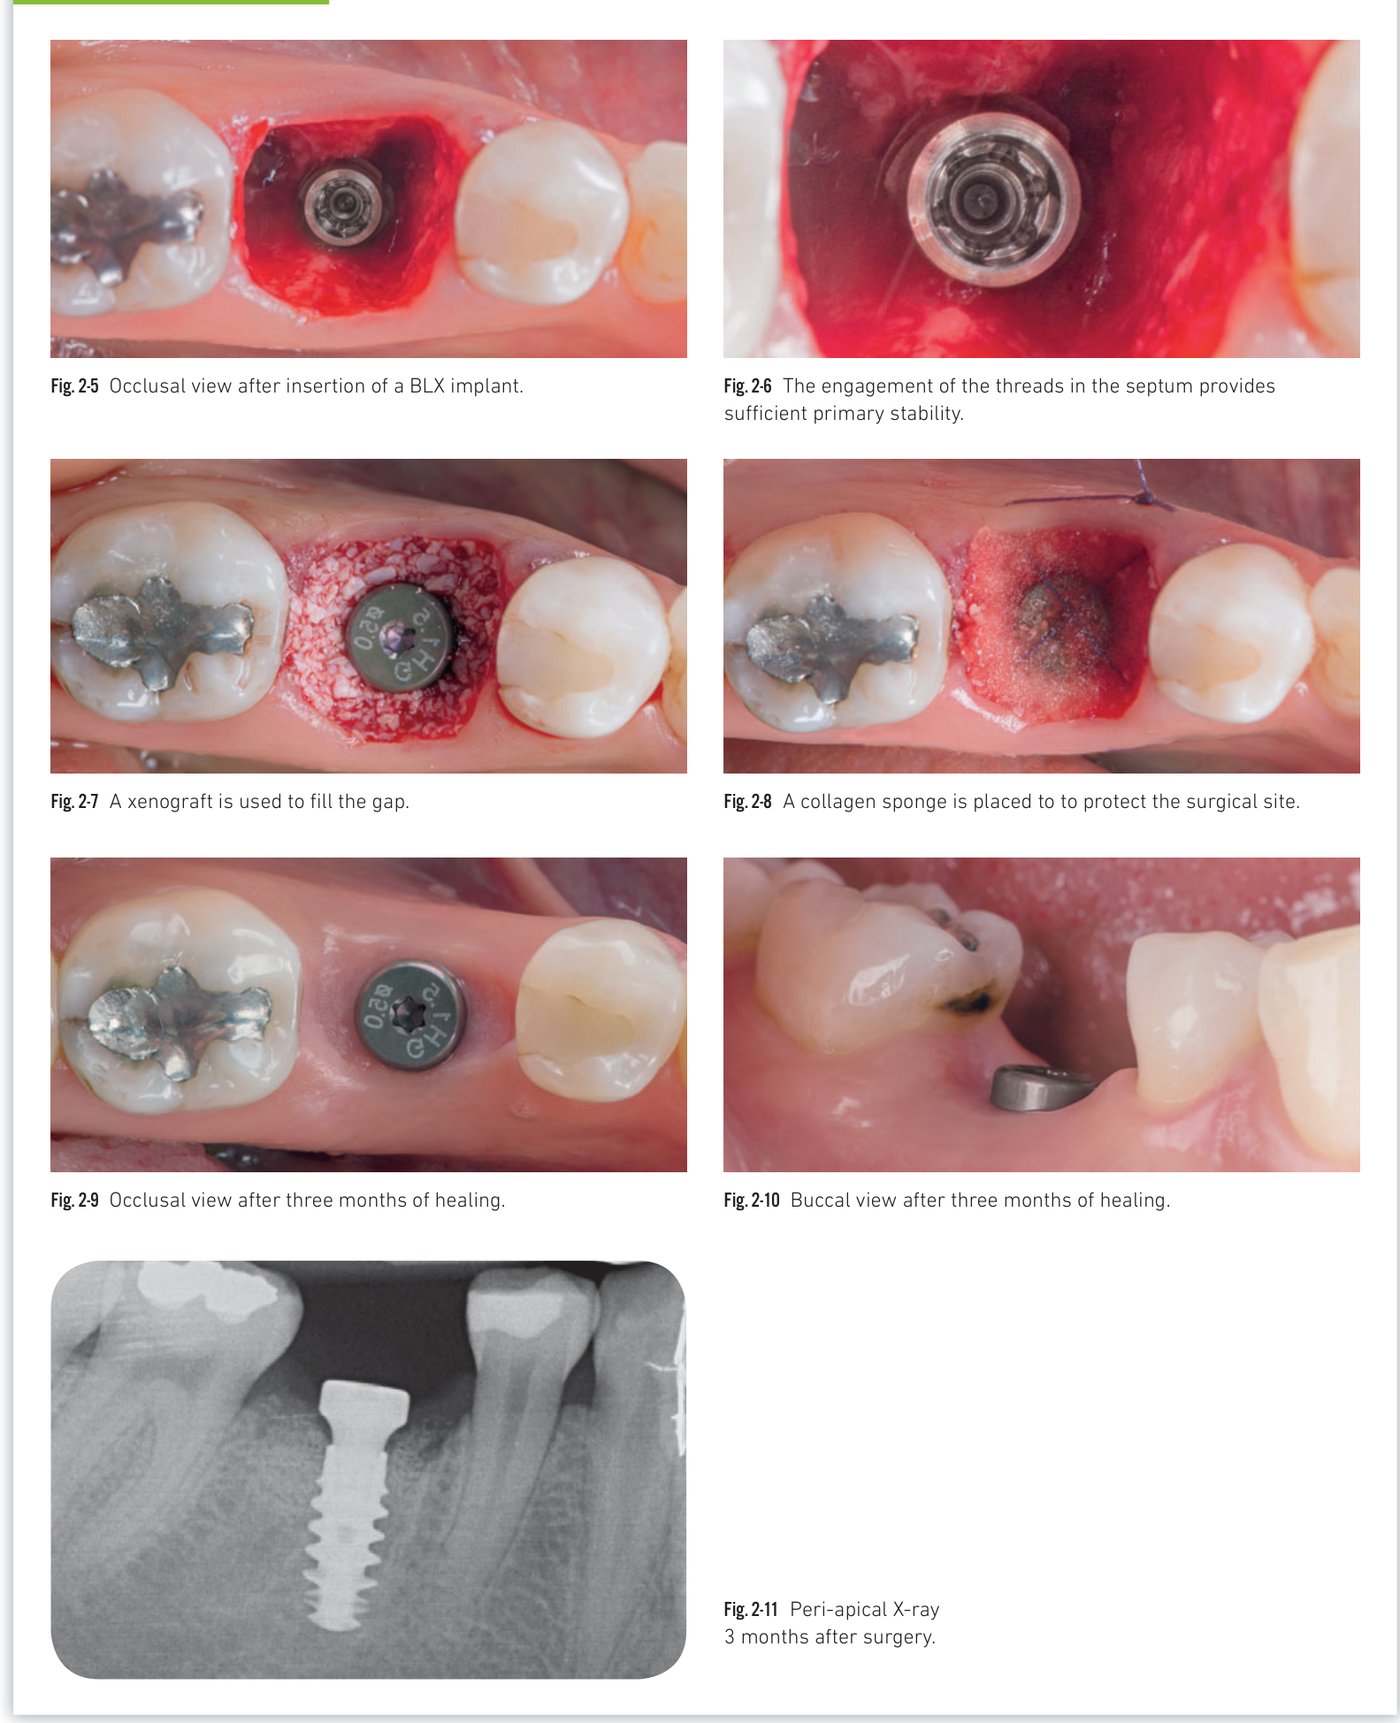

Immediate implant placement in the posterior area

Since an early publication in 1989, immediate implant placement after single-rooted tooth extraction has become a regularly proposed procedure, since successfully extended to multirooted teeth. Cumulative survival rates for implants placed immediately after molar extraction are comparable to those placed in healed sites. The essential factor for success is initial implant stability via apical and/or lateral bone. At a molar extraction site, primary stability may be difficult to achieve due to socket size, poor bone quality, or anatomical limitations (maxillary sinus, mandibular canal). The specific design of the BLX allows satisfactory primary stability even in a very reduced septum.

Clinical situation 2, page 1: Preoperative view, atraumatic extraction, and BLX insertion

Clinical situation 2, page 2: Xenograft filling, collagen sponge, healing, and peri-apical X-ray